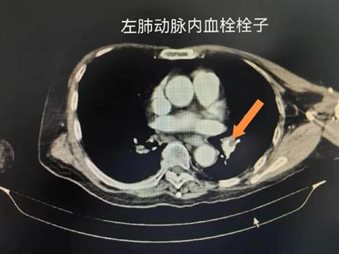

CTPA表现:直接征象为肺动脉内充盈缺损,根据形态可分为中心型(栓子位于血管中心,周围环绕对比剂,呈“轨道征”)、偏心型(栓子附着于血管壁,占据部分管腔)及完全阻塞型(血管腔被栓子完全填充,远端血管不显影);间接征象包括肺组织灌注缺损(对比剂分布不均,栓塞区域密度减低)、肺梗死灶(胸膜下楔形高密度影,边缘模糊,增强扫描无强化)、胸腔少量积液、右心室扩大等。